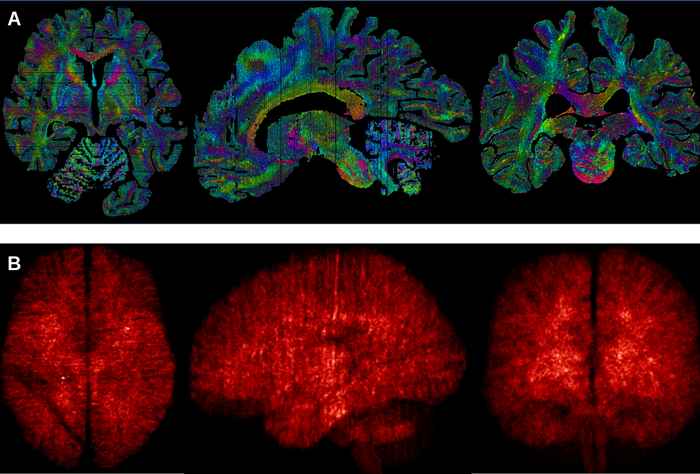

An exhaustive map of the human brain has been a long-sought goal of neuroanatomists. Noninvasive imaging techniques such as magnetic resonance imaging (MRI) allow scientists to investigate the healthy living human brain but provide only limited anatomical detail. A higher level of detail can be obtained by using microscopy on brains from deceased donors, generally focusing on small brain structures imaged in 2D. Now a team led by scientists from the UvA, have combined MRI and microscopy to produce 3D images of two entire brains with a previously unmatched level of detail. Their findings have been published in the journal Science Advances.

The UvA team worked for over five years, alongside researchers from the Max Planck Institute in Leipzig, to build a bridge between ultra-high field MRI and microscopy approaches to creating images of the brain. Two human brains donated to science were placed in the MRI scanner for 21 hours, and afterwards examined under the microscope. The MRIs were then combined with the microscopy slides, resulting in images of the brains which allow for exploration at a 200mm (0.2mm) level of detail.

The researchers used an ultra-high field 7 Tesla MRI system, which has a more powerful magnet than the MRI systems routinely used in hospitals. The MRI software was programmed specifically for these studies by the researchers to accommodate the differences between living and preserved tissue. During the cutting of the tissue, each section was photographed individually, so that it could be used later to digitally correct tissue deformation in microscopy sections. Individual brain sections were placed on specially ordered glass slides, and processed with custom-built laboratory equipment.

After digitisation of the individual microscopy slides, new algorithms were created by the researchers to correct for the tissue deformation resulting from the cutting and microscopy processing. After weeks of uninterrupted calculations, the researchers were finally able to create full reconstructions of two individual brains.